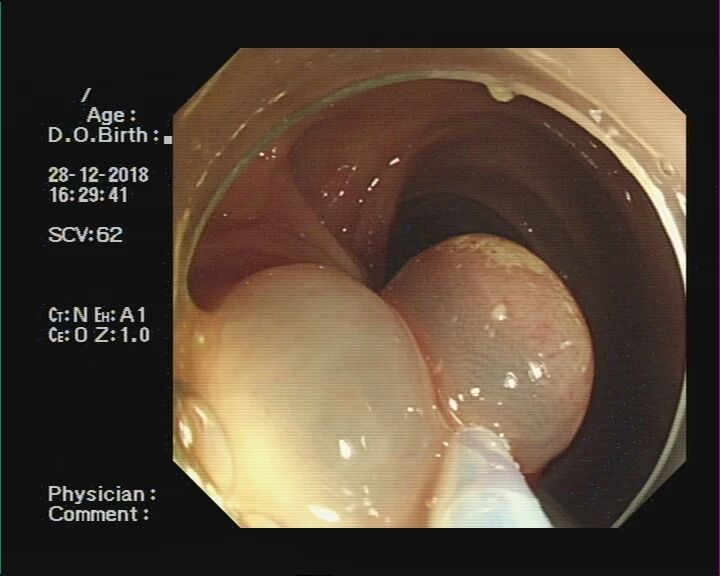

让我们通过肠镜下图片,来了解一下息肉切除的几个步骤:

二、不同的息肉要采取不同的切除方法:

2. 广基大息肉:

直径<2cm的:可采用内镜黏膜切除术(EMR)治疗,即先在病变黏膜下注射生理盐水抬起病变,再用圈套器电切除息肉。

对于直径>2cm的广基大息肉和平坦型病变,即大肠侧向发育型肿瘤(LST):如果选择EMR治疗,只能通过分块切除的方法,但该方法复发率较高,且不能进行准确的病理检查;故优先推荐采用内镜黏膜下剥离术(ESD),大块、完整的切除病变,并进行完整、准确的病例评估。